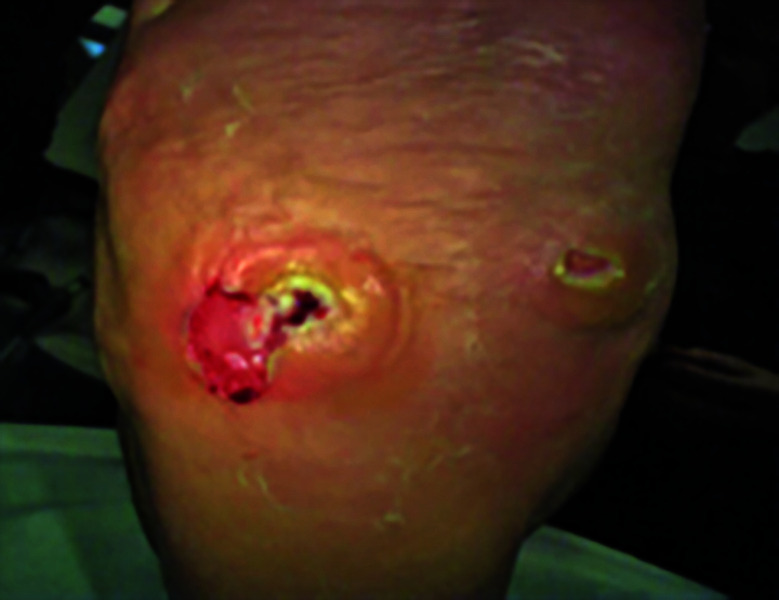

Charcot神经关节病累及足部是糖尿病的一种常见且潜在的破坏性并发症。除了良好的糖尿病控制,外科鞋和定期足部治疗,纠正足部畸形,防止溃疡,深部感染和肢体丧失,现在已经很好地建立了。血管功能不全在这组患者中很常见,传统的血管重建术并不总能成功治愈溃疡和治疗重症缺血。它会影响伤口和骨头的愈合。我们报告了在传统血运方法未能纠正严重缺血的情况下,成功使用改良的胫骨皮质横向运输技术(TTT)。我们已经用这种技术成功地治愈了软组织和骨骼。如何引用本文:Al Omar H, Lahoti O, Edmonds M,等。缺血Charcot中足重建联合胫骨外侧皮质横向转运1例。创伤肢体重建2025;20(1):50-55。

Charcot neuroarthropathy involving foot is a frequent and potentially a devastating complication of diabetes. In addition to good control of diabetes, surgical shoes and regular podiatric treatment, correction of foot deformity to prevent ulceration, deep infection and limb loss are now well established. Vascular insufficiency is common in this group of patients and traditional revascularisation procedures do not always succeed in healing ulcers and treating critical ischaemia. It compromises wound and bone healing. We report successful use of a modified technique of tibial cortex transverse transport (TTT) in a case where traditional revascularisation methods failed to correct critical ischaemia. We have achieved successful soft tissue and bone healing using this technique.